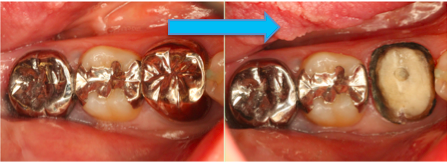

でもね、この画像をみて下さい。

わわっ、銀歯を取ったら周りが黒くなってる。

保険診療では、型取りの精度がまぁまぁなものを使うルールになっています。欧米などで開発された精度の良い、高い型取りは、国の予算オーバーで買えないんです。

もちろん保険診療の型取りも問題ない範囲ではありますけどね。

そういうことか。でも実際、詰め物、被せ物の色の違いは分かっても、型取りの材料の違いのことまでは分からないもん。

まぁそうですよね。保険診療と自由診療、白か銀、色の違いだけだと思っていませんでしたか?